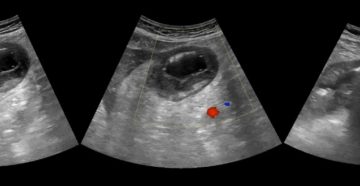

Диффузные изменения печени и поджелудочной(Гепатомегалия) — что это такое? Ставим лайки и подписываемся на канал….